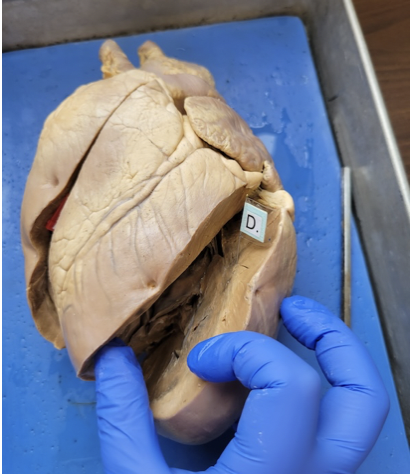

what is this

the left atrium